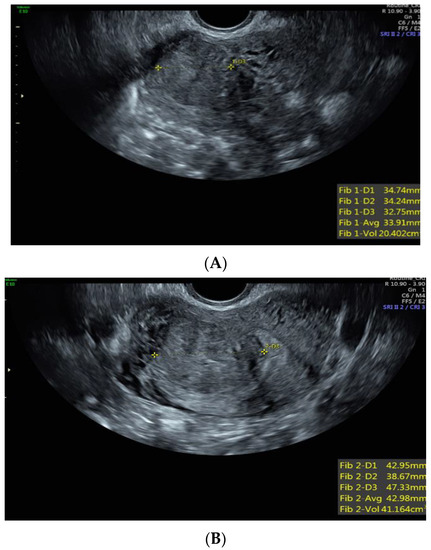

Case 4: A 38-year-old Black patient presented with pelvic pain and heavy menstrual bleeding due to a 10 cm subserosal fundal uterine fibroid (Figure 3). She underwent a robotic hysterectomy with bilateral salpingo-oophorectomy, which confirmed a leiomyoma with features of FH deficiency; germline genetic testing was negative for known pathogenic mutations.

Figure 3. Subserous, fundal, homogeneous uterine fibroid.